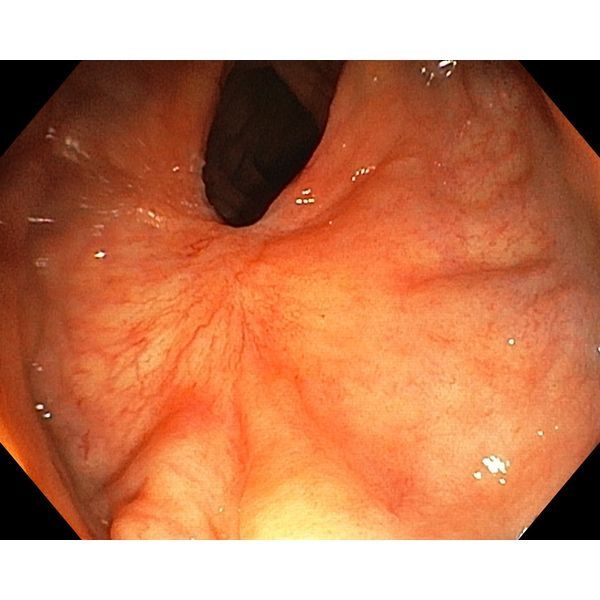

- При ФКС-контроле (фиброколоноскопии) от 31 августа 2022 года — полный регресс опухоли.

- ФКС-контроль от 1 декабря 2022 года — опухоль не определялась. Контрольная биопсия с рубца — слизистая кишки без атипии.

На фоне проведённой химиолучевой терапии достигли полного регресса опухолевого процесса. Пациенту в итоге не потребовалась операция — от опухоли удалось избавиться с помощью химиолучевой терапии.